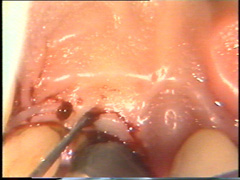

En palatino debe usarse el mismo principio pero la diferencia radica que el tejido palatino es muy fibroso por lo tanto el corte puede realizarse más apical para eliminar la bolsa y poder adaptar mejor el colgajo, que por ser más fibroso es menos flexible que los colgajos bucales.